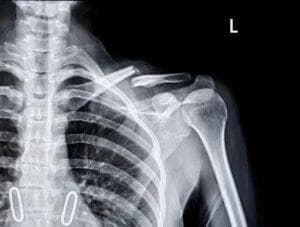

Broken bones, medically known as fractures, range from hairline cracks to complex breaks that require surgery. Even a seemingly minor fracture could lead to extensive medical care. The type of fracture often dictates the level of treatment needed and whether you might face lasting effects.

According to the Centers for Disease Control and Prevention (CDC), fractures from slip and fall incidents consistently rank among the leading causes of hospitalizations. Broken bones can also stem from car accidents, sports mishaps, or even defective products. The required treatment may involve casting, pins, plates, rods, or additional surgeries. Such medical intervention can quickly escalate in cost, especially if you need specialized therapy or a lengthy rehabilitation program.

- Diagnostic imaging such as X-rays, CT scans, or MRIs.